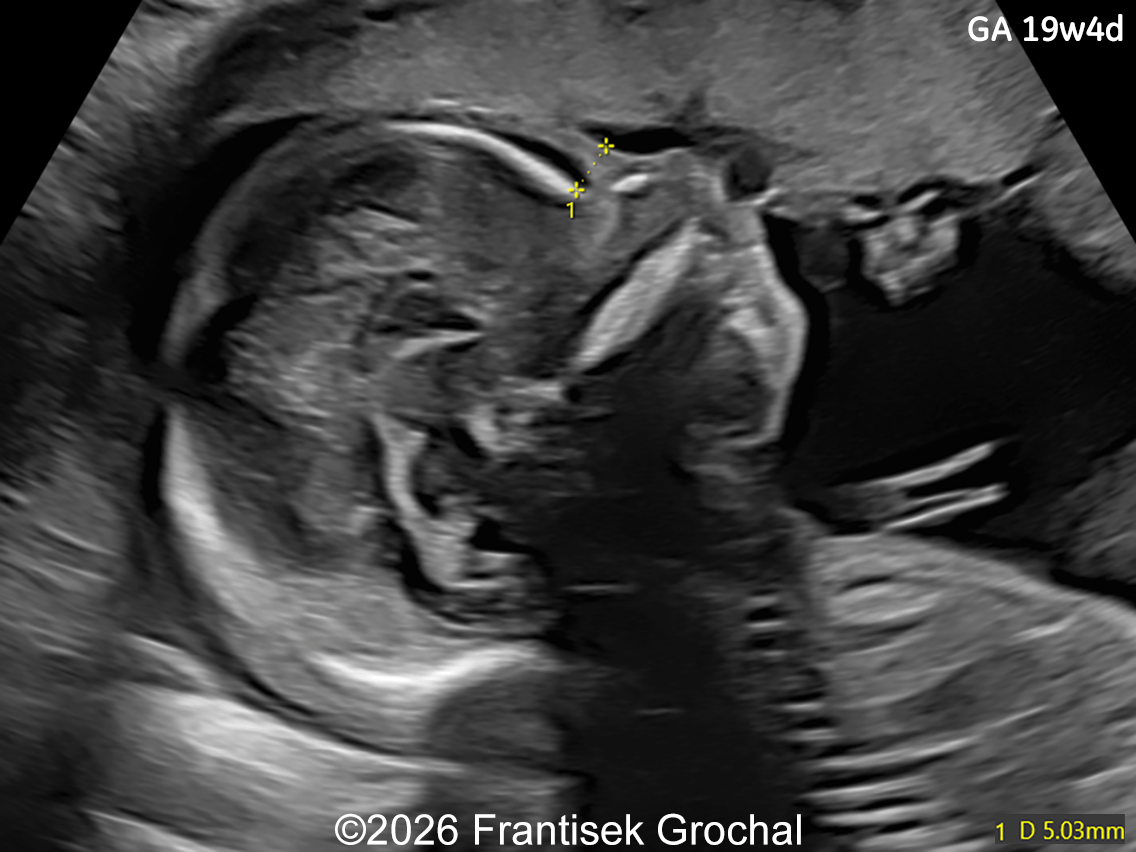

19+4 weeks of gestation; sagittal view of the fetal head demonstrating prefrontal edema, nasal bone hypoplasia, retrognathia, and a short corpus callosum.

Image 1 19+4 weeks of gestation; sagittal view of the fetal head demonstrating prefrontal edema, nasal bone hypoplasia, retrognathia, and a short corpus callosum.